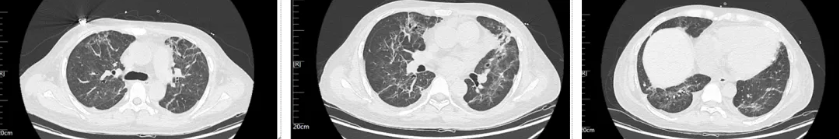

经过治疗后患者病情逐渐好转,呼吸机需氧浓度及PEEP逐渐下调,复查血气氧和指数逐渐好转,9月17日复查胸部CT(见图4),氧合指数165,予拔除气管插管,改日间高流量(流速 40L/min,氧浓度60%)与夜间无创呼吸机辅助通气(IPAP12cmH2O EPAP 5cmH2O FiO2 45%)交替,复查血气氧和指数P/F 182。予逐渐下调氧浓度复查氧和指数进一步升高(见图5),监测患者外周血感染指标超敏C反应蛋白降至基本正常(见图6)。调整鼻导管吸氧,10月7日复查胸部CT双肺慢性及间质改变较前明显吸收(见图7)。监测患者外周血KL-6水平较前明显下降(见图8)。

图4 患者2025年9月17日复查胸部CT

图7:患者2025年10月7日复查胸部CT